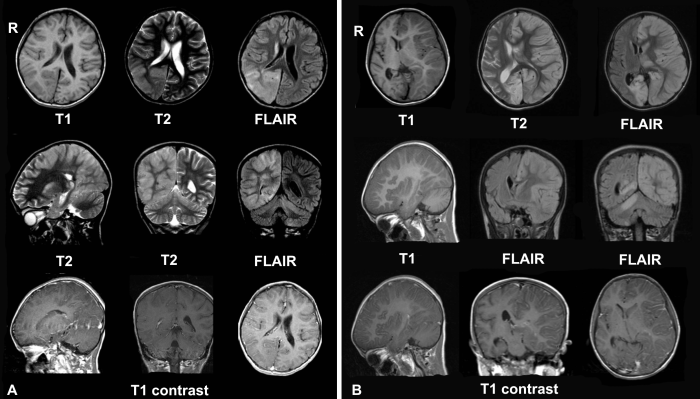

- Pulse Sequences: Different pulse sequences (e.g., T1-weighted, T2-weighted, FLAIR) are used to highlight different tissue characteristics.